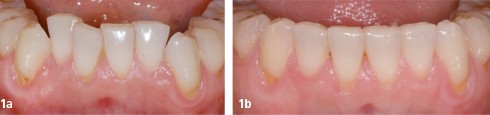

Article réservé à nos abonnés Parodontie et prothèse

Les relations qui unissent prothèse et parodonte sont souvent conflictuelles et complexes. Afin d’éviter ces conflits entre impératifs prothétiques et...